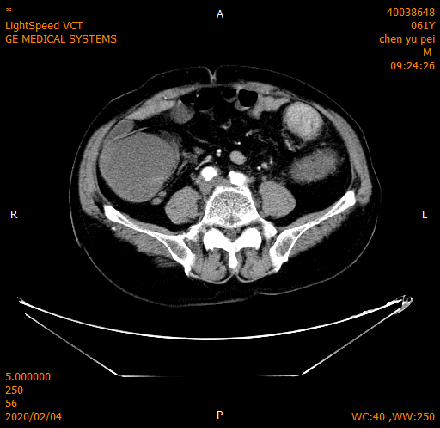

2020-02-04 CT

肝脏多发异常强化灶,考虑转移。

横结肠-降结肠交界处壁增厚强化,请结合消化道检查,腹腔部分肠管扩张积气积液,可见气液平,请结合临床。

2020-02-27 增强CT报告:

肝脏多个略低密度影,考虑转移灶,结合临床;脾脏外缘积液;

胆囊略大;前列腺钙化灶;腹腔积液;左中下腹术后改变;

腹盆腔、后腹膜多发淋巴结,局部肿大;双侧腹股沟小淋巴结。